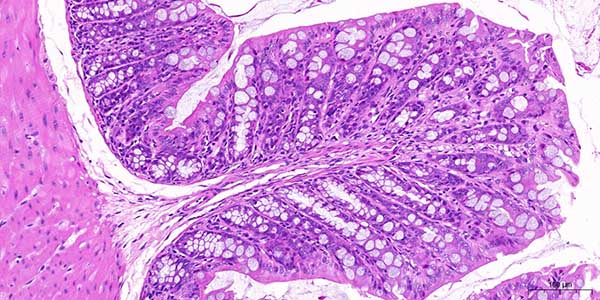

3. 高分辨率与精准成像 清晰细节:支持高倍率(如40x-1000x)光学放大,图像分辨率可达0.2微米/像素,清晰呈现细胞形态、染色特征及微小病灶,辅助精准诊断。 色彩还原:采用多光谱成像和色彩校正技术,确保染色图像真实还原,减少人为误差。